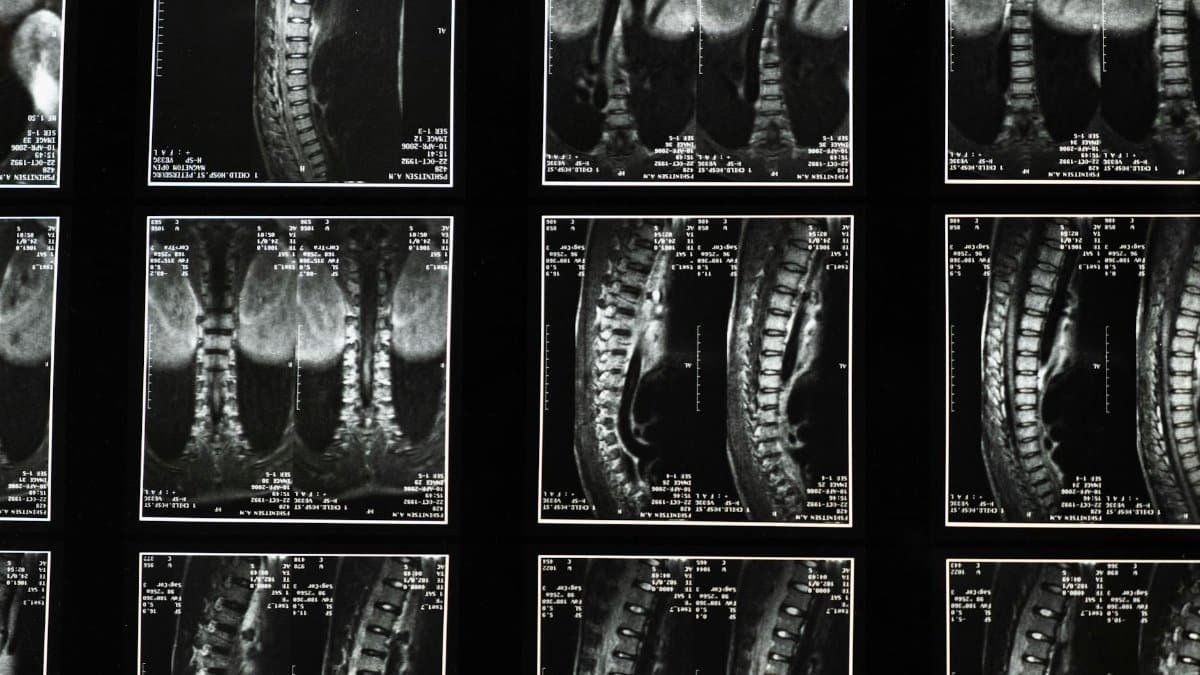

Comprehensive spinal x-ray images, ideal for medical studies and diagnostics.

Photo by cottonbro studio via Pexels